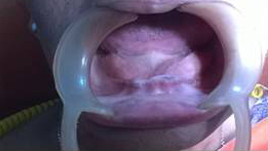

After Placement of Prosthesis

Single Tooth Implant